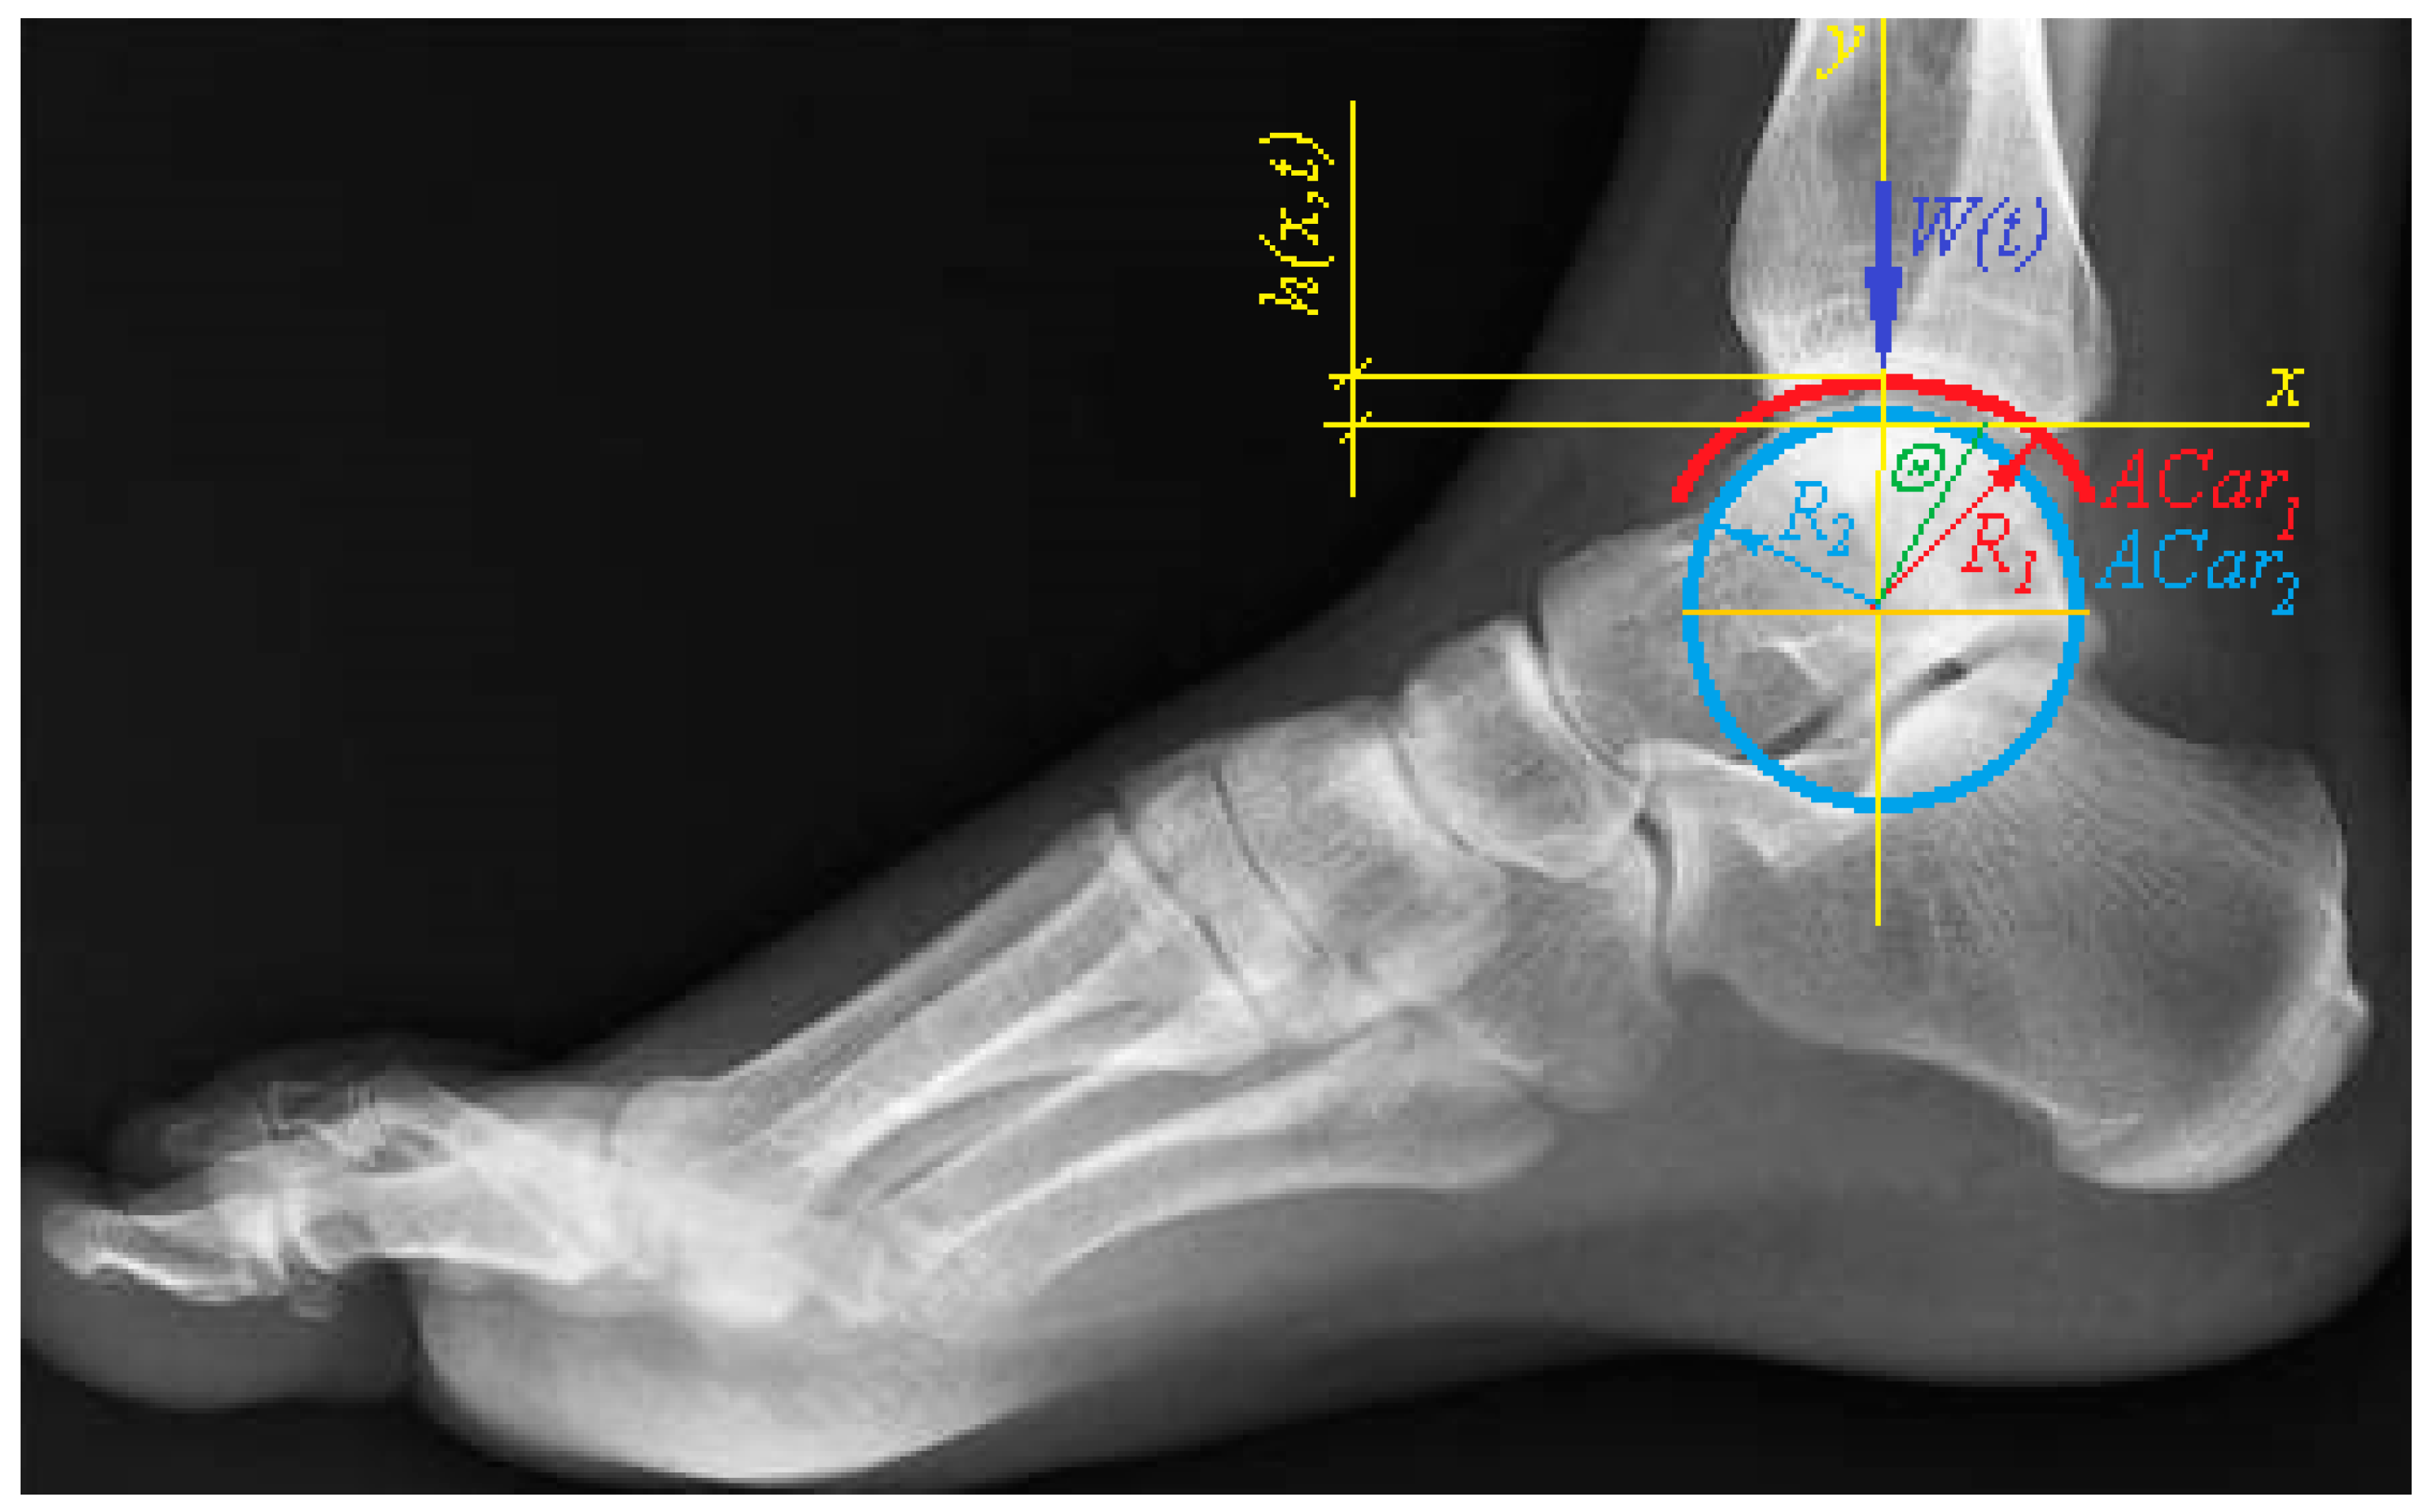

| Effective radius of curvature of the contact of talus and tibia: | |

| Radius of talus curvature | |

| Radius of tibia curvature | |

| Cartesian coordinates of the ankle model | |

| Polar angle: | |

| Polar angle of the ankle model | |